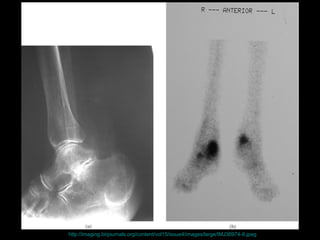

腳掌骨 ( 蹠骨 ) 之壓力性骨折 http://www.mikety.net/X-rays/Fx-mt.ANS.jpeg

http://www.hypertension-consult.com/Secure/textbookarticles/images/106pic6.jpg

http://uwcme.org/site/courses/legacy/threehourtour/images/LatCalcaneus1Arrows.jpg

http://imaging.birjournals.org/content/vol15/issue4/images/large/IMJ36974-8.jpeg